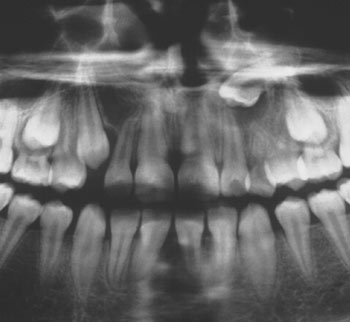

Antal – Over- eller undertal af tænder bedømmes almindeligvis præcist på et panoramabillede. En enkelt undtagelse kan dog være små overtallige tænder i overkæbefronten (mesiodens), som grundet «spøgelsesskygger» fra cervikalhvirvlerne kan være vanskelige at se (Fig. 6A og B).

Fig. 6 A: Beskåret panoramabillede, hvor det er svært med sikkerhed at diagnosticere «mesiodens» regio +1. B: Intraoral, periapikal optagelse regio +1 (samme patient som vist i Fig. 6A) viser tydeligt tilstedeværelse af «mesiodens» (pile).

Retentioner – Retinerede tænder og deres lejring vil almindeligvis fremgå tydeligt af et panoramabillede. Den mesio-distale udstrækning af den retinerede tand kan ofte anvendes til at bedømme tandens facio-orale beliggenhed i forhold til nabotænder. Forudsat at panoramabilledet er uden højre-/venstresidig distorsion, vil en retineret tand, som fremtræder «bred» og uskarp sammenholdt med den tilsvarende tand på den anden side af midtlinjen, være beliggende oralt (Fig. 7), mens en retineret tand, som fremtræder «smal» og uskarp, vil være beliggende facialt. Reglen skal imidlertid bruges med varsomhed på tandtyper, som har tendens til at variere i størrelse.

Fig. 7. Beskåret panoramabillede af barn med retention af +3. Det «brede» udseende af +3 i forhold til 3+ indikerer palatinal beliggenhed af +3.